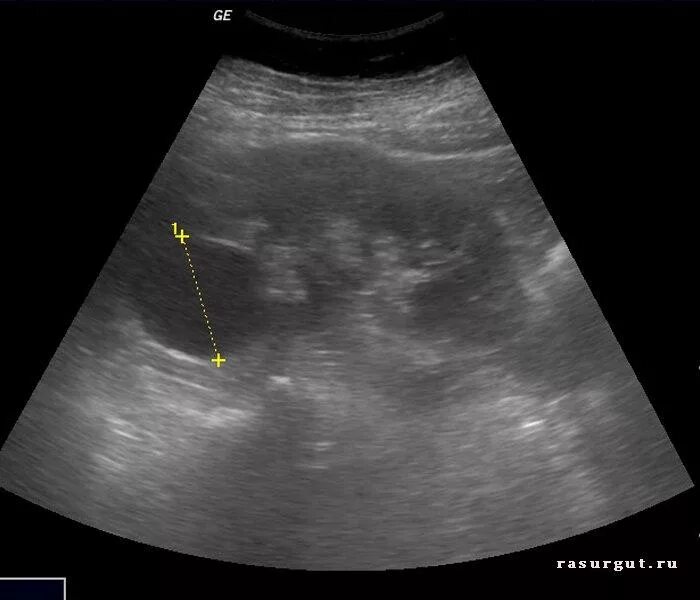

С анэхогенным содержимым что это